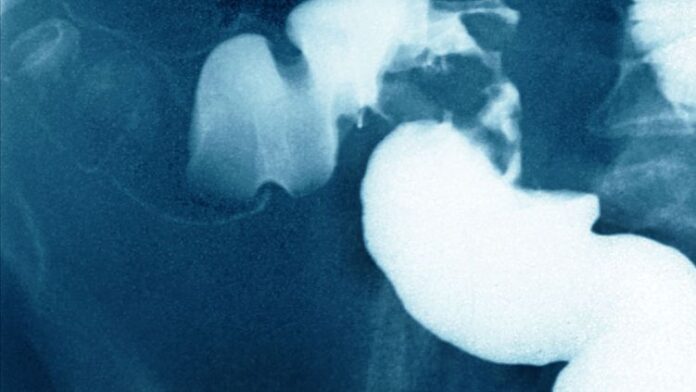

Le cancer colorectal est le troisième cancer le plus fréquent, et il cause plus de 17.000 décès chaque année en France. Des cancers qui atteignent désormais plus fréquemment les personnes entre 40 et 50 ans. Normalement les plus de 50 ans sont concernés, c’est ce que révèle une récente étude américaine.